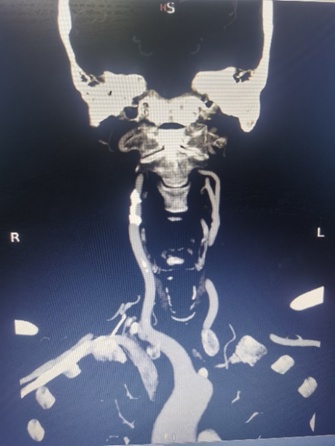

刘大爷这类患者颈动脉分叉位置高、病变斑块长,不适宜传统颈动脉内膜切除术,同时他主动脉有较多溃疡斑块,远端颈动脉扭曲,因此传统经股动脉入路颈动脉支架植入术(TFCAS)风险较大。经华山医院血管外科团队严格的术前评估后,团队决定应用TCAR技术规避CEA和TFCAS技术的不足,为刘大爷进行治疗。手术仅历时1小时便顺利完成,术后刘大爷恢复良好,脑缺血症状消失,于第三天顺利出院。

术前影像